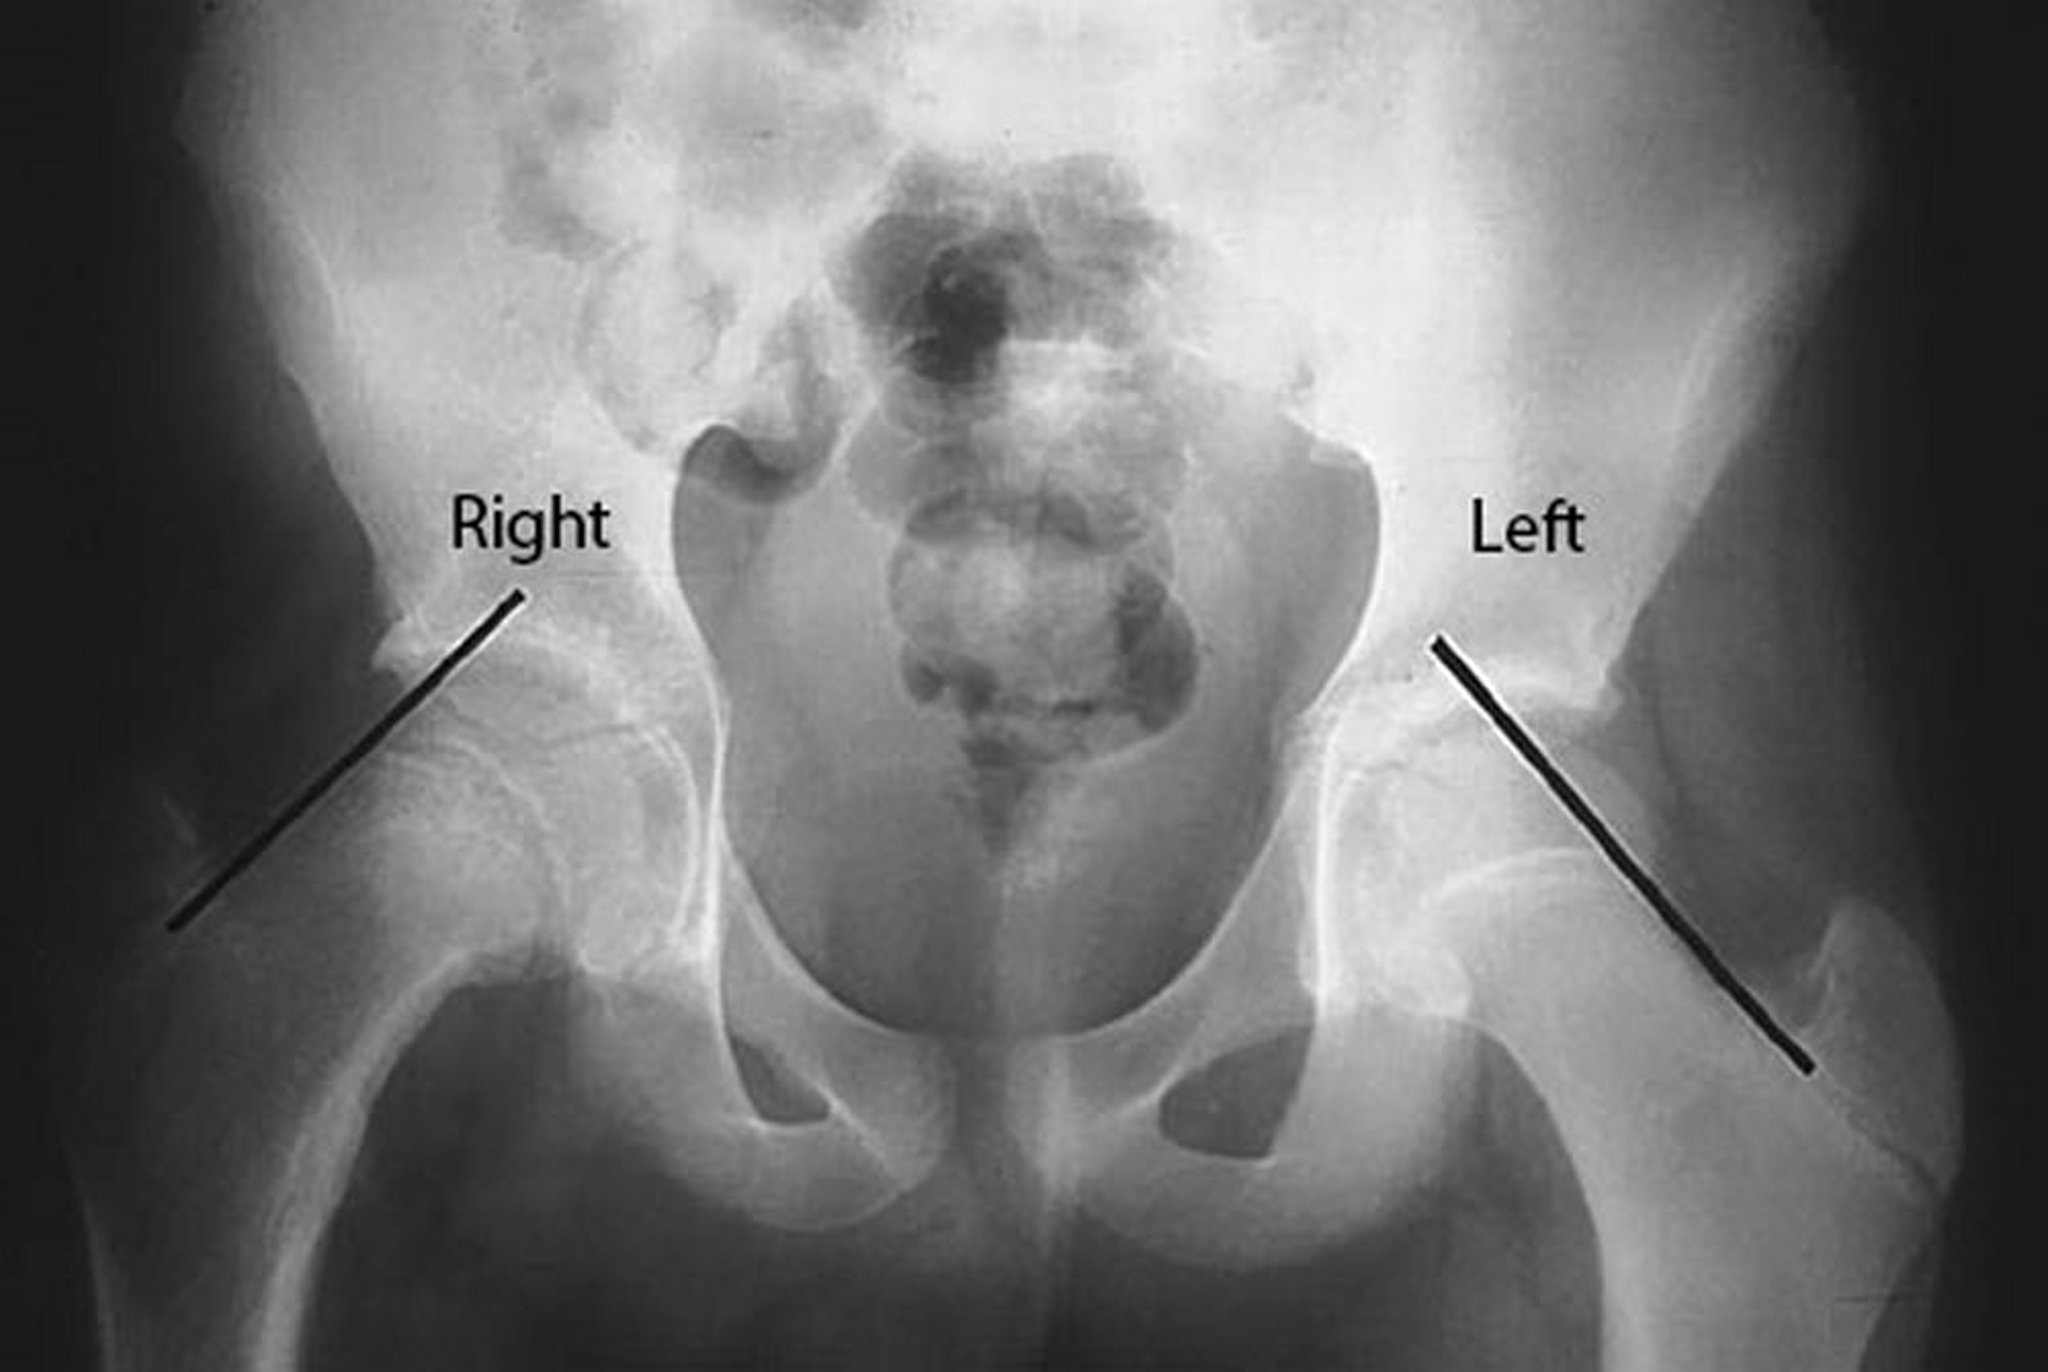

Klein lines are drawn on the superior border of the femoral neck in this patient with slipped capital femoral epiphysis (SCFE) of the right hip. Note that the femoral head is below the Klein line on the affected right side, whereas a significant portion of the femoral head is above the Klein line on the unaffected left side.

By permission of the publisher. From Campbell R Jr: Current Orthopedic Diagnosis and Treatment. Edited by JD Heckman, RC Schenck, and A Agarwal. Philadelphia, Current Medicine, 2002.